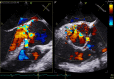

Figure 6

Mid-oesophageal aortic valve long/short axis view with colour Doppler imaging, disclosing severe aortic regurgitation that had regressed with respect to the previous study.